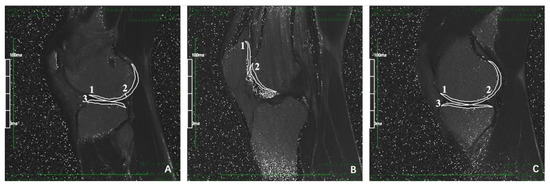

The MRI data of 3D-DESS sequence were imported into Siemens knee cap (version 1.5) workstation for automatic recognition of knee cartilage. The software could automatically divide articular cartilage into eight sub-regions [,]: patella (P), femoral trochlea (TrF), anterior area of lateral femoral condyle (aLFC), posterior area of lateral femoral condyle (pLFC), and anterior area of medial femoral condyle, (aMFC), posterior area of medial femoral condyle (pMFC), lateral tibia plateau (LT), medial tibia plateau (MT). The volume of cartilage in each subregion was obtained by manual fine-tuning. The aLFC and pLFC were divided by the posterior horn of the lateral meniscus, and the aMFC and pMFC were divided by the posterior horn of the medial meniscus. The specific operation interface of the software was shown in Figure 2, and the 3D model established by the software according to the preoperative knee cartilage of the patient is shown in Figure 3.

Figure 3.

3D model of knee joint cartilage. The 3D reconstruction model of complete knee cartilage was automatically divided into 8 subregions: P, TrF, aMFC, pMFC, aLFC, pLFC, MT and LT by Siemens knee cap (version 1.5). Different cartilage subareas are marked with different colors. The corresponding cartilage subareas of each color are shown in the far right of this figure. P, patella. TrF, femoral trochlea. aLFC, anterior area of lateral femoral condyle. pLFC, posterior area of lateral femoral condyle. aMFC, anterior area of medial femoral condyle. pMFC, posterior area of medial femoral condyle. LT, lateral tibia plateau. MT, medial tibia plateau.